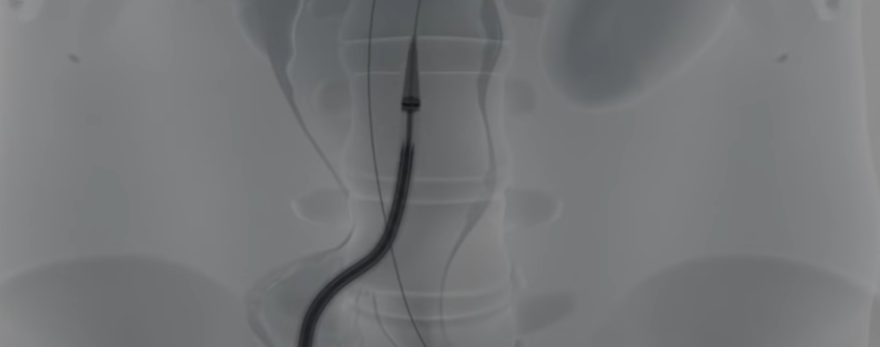

Nellix recupera o CE Mark

A Endologix anunciou o restabelecimento da certificação europeia CE Mark para o sistema Nellix (EVAS). Em janeiro de 2019, a empresa anunciou que a certificação CE Mark havia sido suspensa em resposta a um recall voluntário e a circulação de notificações de segurança.

Matt Thompson, diretor médico da Endologix, declarou: “Continuamos acreditando que o sistema Nellix tem o potencial de transformar o tratamento de pacientes com aneurismas da aorta abdominal infra-renal. Esse tratamento continua gerando resultados positivos quando usado em pacientes que estão em conformidade com as indicações anatômicas de uso. Estamos muito satisfeitos com o fato de os dados disponíveis darem base para a reintegração de nossa marca CE e esperamos usar essa tecnologia para melhorar a experiência do paciente e gerar melhores resultados”.